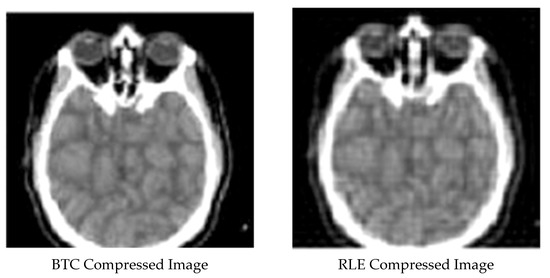

3.5. Block Truncation Coding Technique

3.4. Run Length Encoding Technique

| 6 | Block truncation compressed image | 0.087685188 | 0.66648485 | 47.63287631 |

| 9 | RLE compressed image | 0.48970346 | 0.299972986 | 43.72625764 |